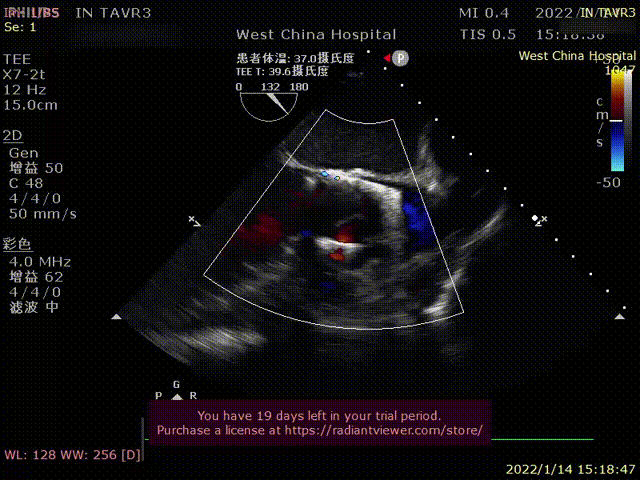

患者为69岁男性,因“活动后胸闷,气紧十年余,加重1月”主诉入院。术前超声提示:左心明显增大,LVDD 82mm,LVEF 26%,主动脉瓣重度狭窄伴重度反流。术后即刻主动脉瓣大量反流消失,超声显示LVDD 65mm,左心较术前显著缩小。

术前超声影像